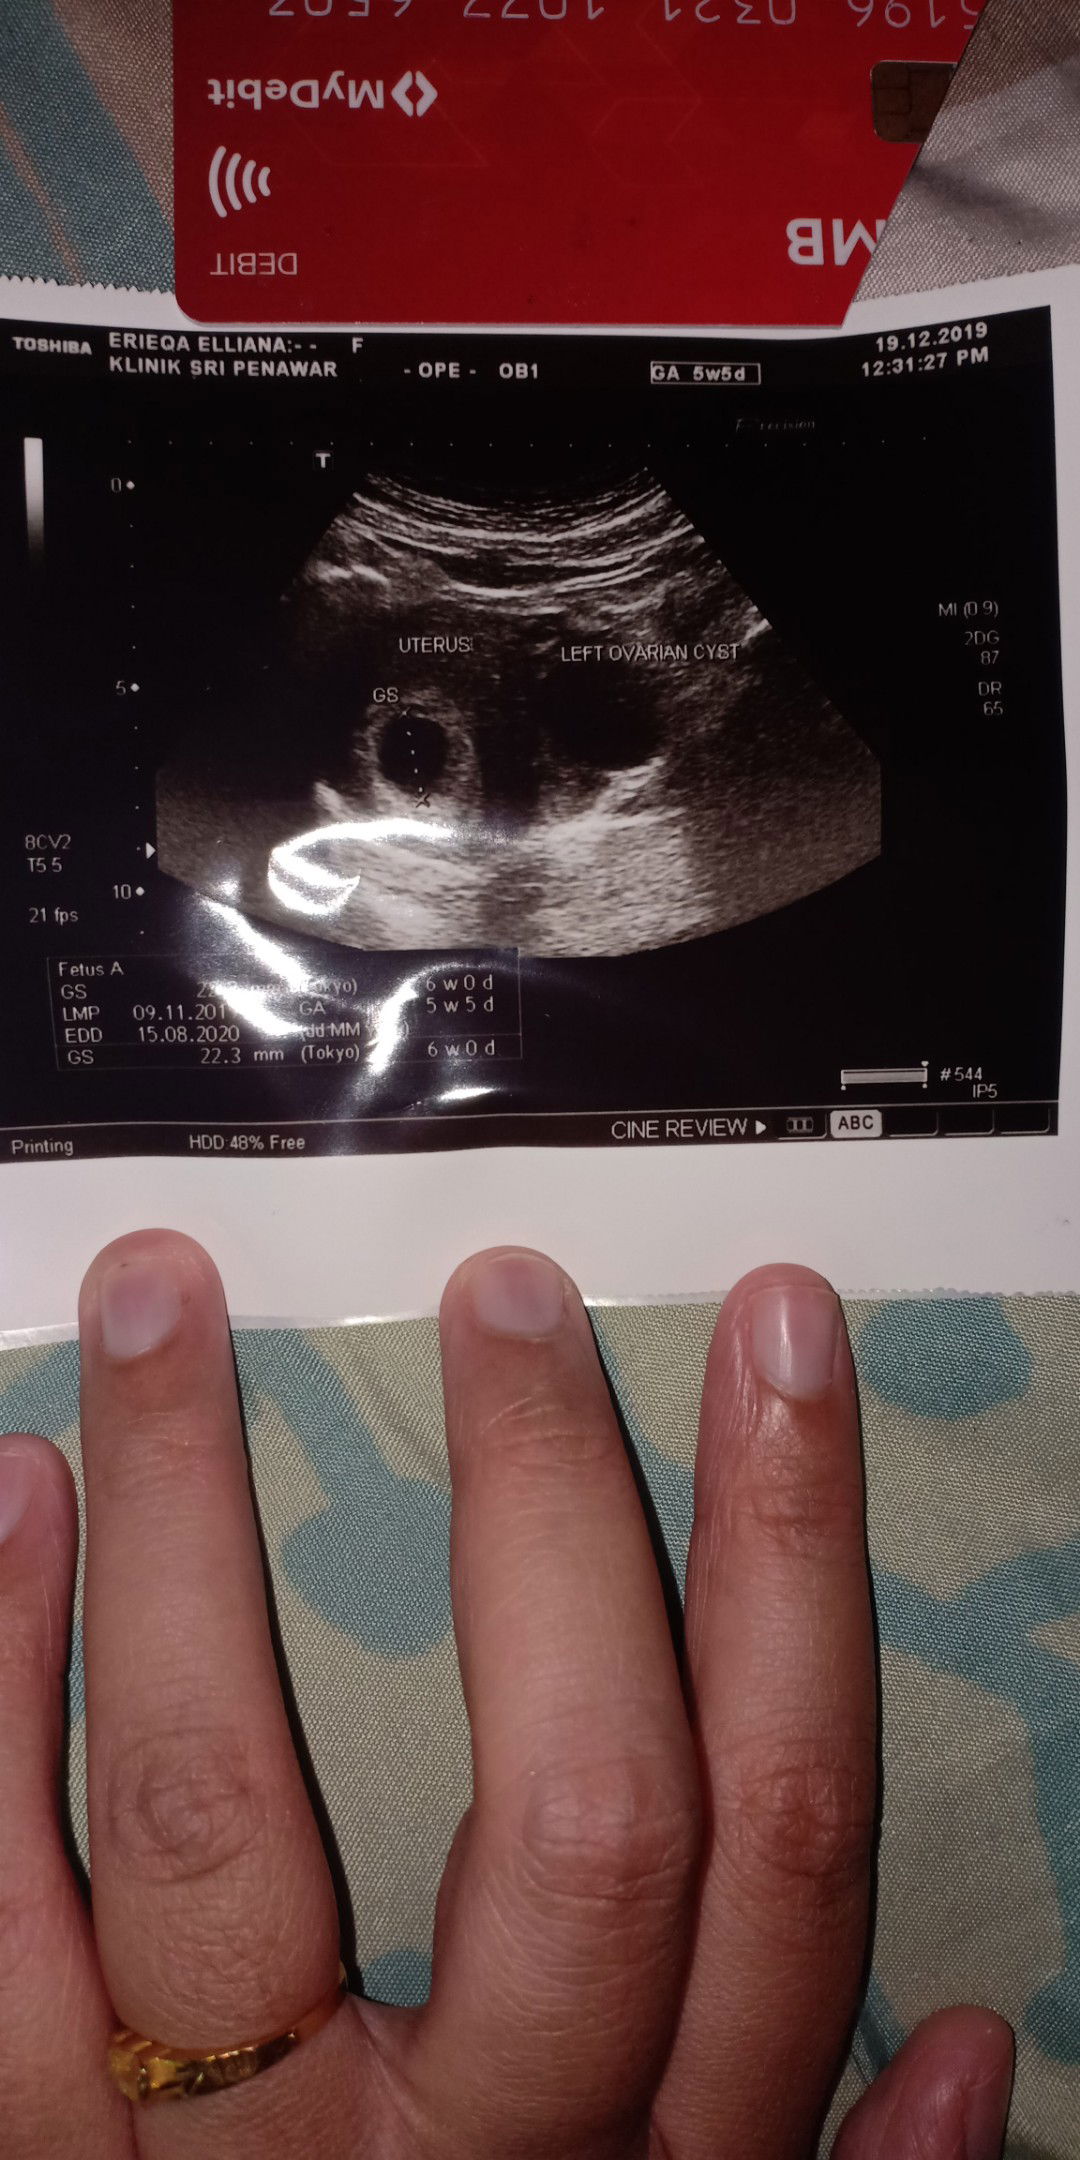

6 weeks pregnancy with ovarian cyst

Hi Salam semua, saya nak tanya pada pakar dan ibu yg berpengalaman. Hari tu saya scan kandungan, doctor suspect Saya ada ovarian cyst belah kiri. Adakah cyst boleh membahayakan kandungan saya? Buat Masa ni kantung xnampak janin lagi..mungkin sebab masih kecil dan awal. Terima kasih.